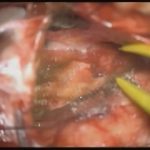

術中写真

摘出 中